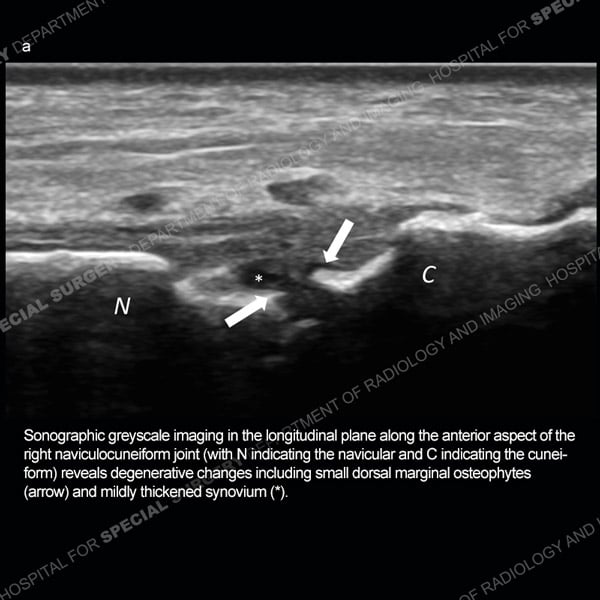

![]() |

Featured Ultrasound of the Month CaseCase 185: 55-year-old woman with right foot pain from naviculocuneiform joint osteoarthritis. |